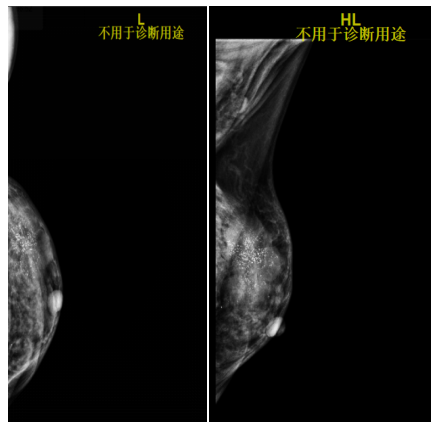

2021-7-29乳腺B超提示:左侧乳腺1-2点钟A环内见大小约21*22*8mm低回声区,边界不清,内见散在强光点,周边可见血流信号。余双侧乳腺腺体形态、结构未见异常。

左侧腋窝见多枚低回声结节,边界清,形态饱满,有包膜,较大者约16*7mm,内可见血流信号。右侧腋窝见多发低回声结节,边界清,有包膜,较大者约10*4mm,血流信号不明显。

影像诊断:左侧乳腺低回声区(BI-RADS:6类);左侧腋窝淋巴结偏大。

图3.乳腺B超(2021-7-29)